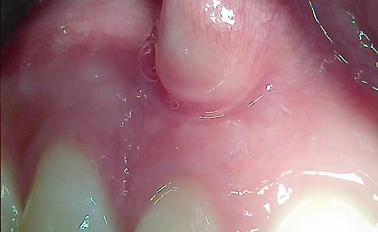

이 글의 핵심 요약 대상: 눈에 잘 띄는 앞니 상실로 인해 외관상 자연스러움과 기능을 동시에 회복하고 싶은 분 핵심: 1mm 미만의 얇은 **순측 골벽(입술 쪽 뼈)**을 보존하며 정밀하게 식립하는 고난도 기술 강점: 0...